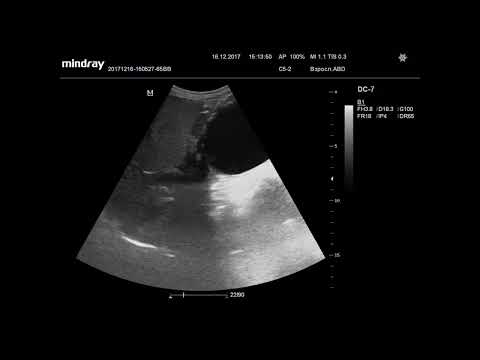

Ультразвуковая диагностика. Доктор Иогансен. Видеопримеры. Выпуск 2. Метастазы в печени. Часть 2.

Представлены вторая часть видеопримеров метастазов в печени, выявленных при ультразвуковом исследовании. Ссылка на Дзен: Ссылка на RuTube: Ссылка на VK видео: Ссылка на YouTube: / @dr.johansen